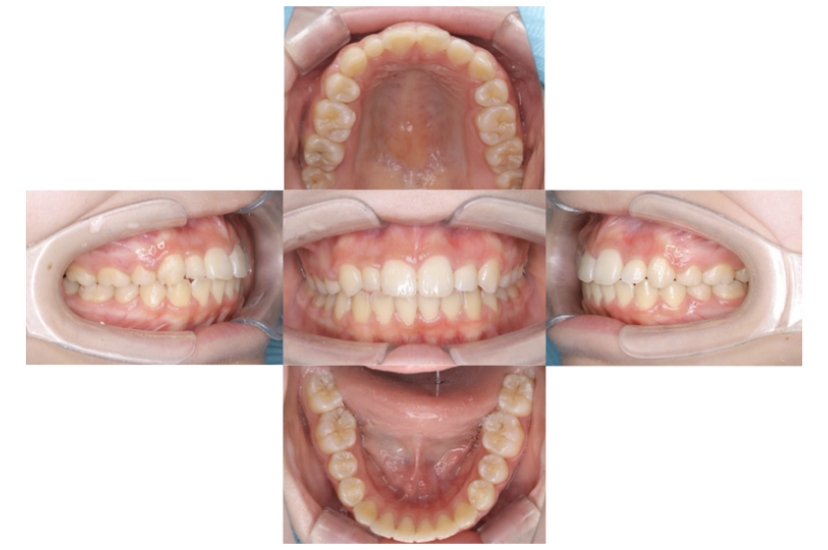

症例1

上顎前突、叢生

抜歯

ブラケット矯正

上下顎叢生、上顎前突(出っ歯、上下の前歯のガタガタ)のケースです。

装置はラビアル(上下表側)で、上顎の小臼歯を2本抜歯を行っています。抜歯したスペースを使って、上の前歯の後方移動と叢生(ガタガタ)と出っ歯の改善を行っています。下は歯と歯の間にIPR(隣接面削合)を行い、スペースを確保し、叢生の改善を行っています。

主訴 前歯のガタガタと出っ歯が気になる。

年齢・性別 47歳 女性

お住まいの地域 神奈川県川崎市

治療方針 抜歯スペースおよびIPRを利用して上前歯の叢生(ガタガタ)の改善

抜歯部位 上顎左右第一小臼歯

使用装置 ラビアル(上下表側)、顎間ゴム

治療期間 2年0か月

治療回数 15回

リテーナー クリアリテーナー

BEFORE

AFTER